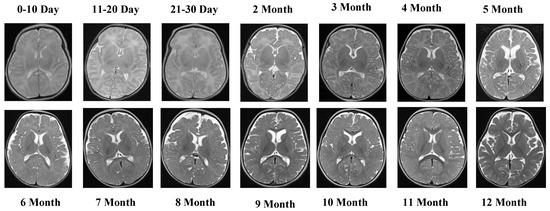

Representative MRI slices from the T1 Male sequence are shown in Figure 1, illustrating anatomical consistency across developmental intervals.

Figure 1 illustrates representative MRI scans from the T1 Male sequence across different developmental groups, highlighting the anatomical consistency and quality of the data.

The T1 Male sequence contained 8154 images (6523 for training and 1631 for testing). The data are systematically organized from early neonatal stages (0–10, 11–20, and 21–30 days) to monthly intervals covering 2–12 months. This structured arrangement provides balanced coverage across both early infancy and later developmental stages. Examples of MRI slices from the T1 Female sequence are presented in Figure 2, demonstrating structural variation across neonatal and infant periods.